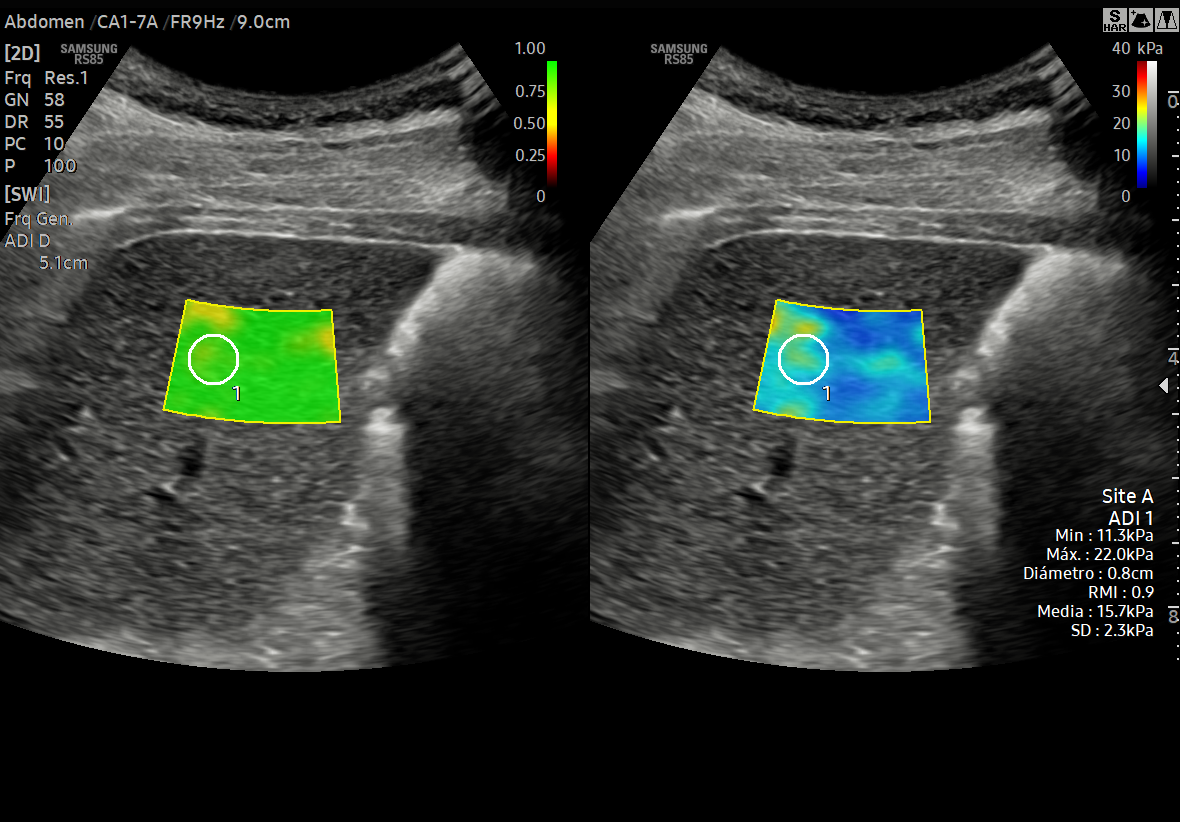

ECOGRAFÍAS ESPECIALIZADAS Elastografía de Hígado Cuantificación de Esteatosis Multiparamétrica de Hígado Elastografía de Tiroides Multiparamétrica de Tiroides Elastografía de Mama Multiparamétrica de Mama Doppler de Pene con sustancia Vasoactiva Multiparamétrica de Ganglios